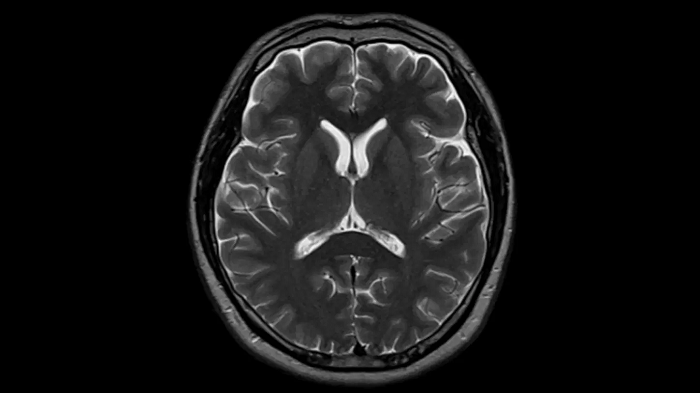

T2 TSE with Deep Resolve

To produce high-resolution images, Deep Resolve, the Al-powered image reconstruction technology gets benefits from intelligent denoising and neural networks.

Deep Resolve Gain & Sharp

0.4 x 0.4 x 5.0 mm2

TA 2:50 min

MAC-ID: 7aaaa0195. Image Credit: Siemens Healthineers